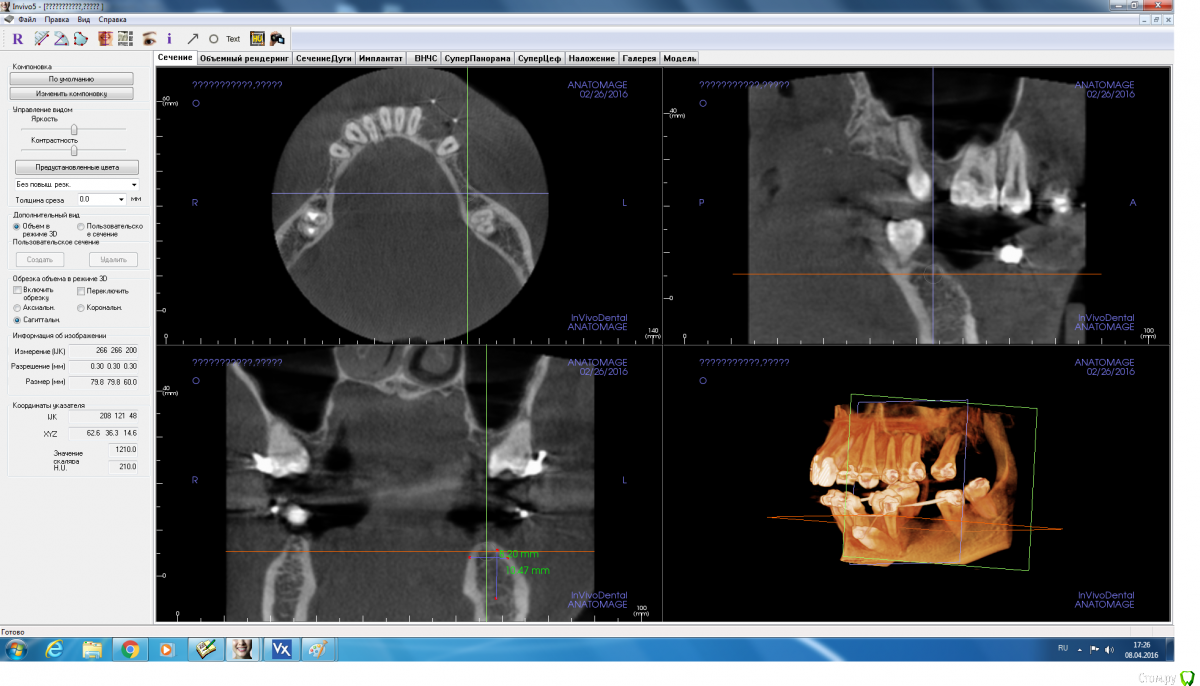

adamskot Опубликовано 8 апреля, 2016 Поделиться Опубликовано 8 апреля, 2016 Коллеги, доброго времени суток.Ретенированный клык уже удален,на его место биоосс и мембрана.Кто как бы поступил в третьем сегменте? заранее спасибо за мнения) Ссылка на комментарий

adamskot Опубликовано 8 апреля, 2016 Автор Поделиться Опубликовано 8 апреля, 2016 Момент, сейчас поправлюТак? Ссылка на комментарий

adamskot Опубликовано 9 апреля, 2016 Автор Поделиться Опубликовано 9 апреля, 2016 Пойду на аутоблок, с ретромолярной области, чтобы восполнить потерю вестибулярно в позиции 35.В позиции 36 поставлю одновременнно через 4 мес с 35. Будет более бюджетно, нежели мембрана,ксено и скребок...Надеюсь, срезы сейчас удачны для обзора)) Ссылка на комментарий